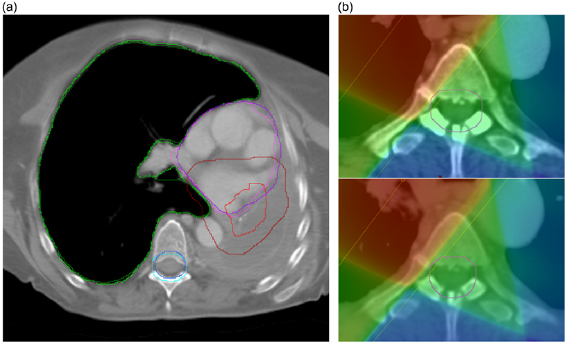

For DVHs calculated using the rCT structures, deviations from the gold standard rCT values were small across all patients. The largest deviation of 2.0% related to the CTV + 1 cm V95% for a single patient where there was a major reduction in tumour size in the CBCT which was not fully captured in the dCT. For this patient the need for a replan would be clear from visual inspection of the images.

The DVH values that were calculated using the deformed pCT structures were clearly less well matched to the gold standard. On visual inspection, it was clear that the deformed structures were, in some cases, very different to the directly outlined rCT structures (figure 8(a)). The reasons for this are discussed in detail in the following sections. In addition, for a single patient, there was a large spinal canal + 5 mm maximum dose deviation of 9.4% which occurred even though the structures were visually very similar. Here, the directly outlined structure slightly overlapped into a treatment field whereas the deformed structure did not (figure 8(b)). The implications of this are also considered in the next section.

Figure 8. (a) Deformed pCT (light) and directly outlined rCT (dark) structure comparison for a single patient—the right lung (green), spinal canal + 5 mm (blue), heart (purple) and CTV + 1 cm (red) are overlaid for both structure sets on a single transverse slice. Whilst the lung and spinal canal are similar, the CTV + 1 cm outlined on the rCT is much larger than the deformed CTV + 1 cm. Although the heart appears well-matched on this slice, the heart that was outlined on the rCT extends further superiorly than the deformed structure. (b) Directly outlined spinal canal + 5 mm (top) compared with deformed spinal canal + 5 mm (bottom). Although the structures are similar, there is a noticeable difference in maximum dose as the directly outlined rCT structure slightly overlaps the treatment field whereas the deformed structure does not.

Download figure:

Standard image High-resolution imageA comparison of the rCT gold standard DVH with dCT DVHs using both directly outlined rCT structures and deformed pCT structures is shown at figure 9.

Figure 9. Gold standard rCT DVH overlaid with dCT DVHs calculated using either directly outlined rCT structures 'dCT (rCT)' or deformed pCT structures 'dCT (dCT)' for a single patient. The dCT (rCT) matches the rCT DVH well, whereas the dCT (dCT) is noticeably different for all structures with the exception of the lungs. It should be noted that spinal canal + 5 mm differences are largely attributable to outlining differences—the rCT structure extends further than the pCT (and hence the deformed) structure in both the superior and inferior directions. However, this is not an issue as only Dmax is considered for serial structures such as this.

Download figure:

Standard image High-resolution imageDemonstration of clinical application